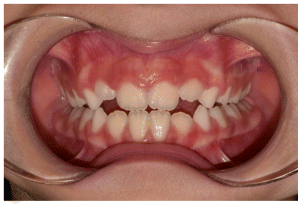

The patient was a young female presenting with a Class III dento-skeletal malocclusion, which was treated using the AMCOP® TC appliance. A comprehensive diagnostic protocol was carried out both before and after treatment, including orthopantomography (Figure 2–3), postero-anterior teleradiography (Figures 4, 5), latero-lateral cephalometric radiography (Figures 6, 7), cephalometric analysis (Tables 1, 2), as well as extraoral (Figures 8, 9) and intraoral photographs (Figures 10, 11). The extraoral examination revealed an edge-to-edge incisal relationship and the presence of a midline diastema. Pre-treatment cephalometric analysis (Deltadent® Lana, Bolzano, Italy) confirmed the diagnosis of a skeletal Class III malocclusion. The treatment plan involved the use of the AMCOP® TC appliance. The patient was instructed to wear the device for two hours in the afternoon and throughout the night for the first six months, followed by nighttime use only for an additional six months. Upon completion of the treatment, the patient achieved a Class I occlusion, with correction of both overjet and overbite. Additionally, the device facilitated tongue re-education and contributed to the postural realignment of the first cervical vertebra.